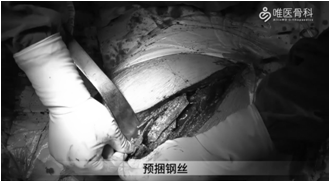

①充分冲洗后给予股骨髓腔扩髓、预绑钢丝,然后安装股骨假体(MP)远端,安装MP假体近端试模。